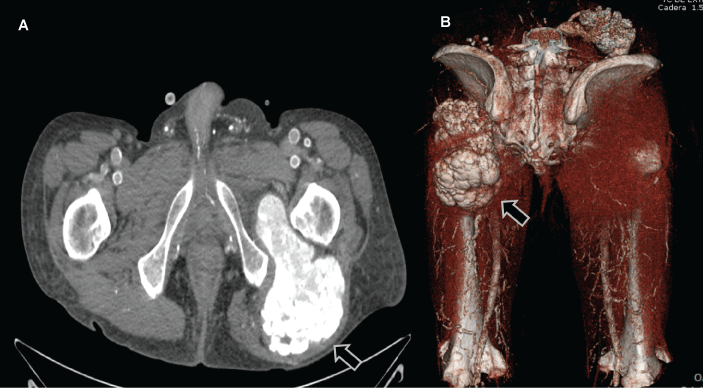

An axial computed tomography (CT) scan (Figure 1A) and posterior projection of 3D CT scan (Figure 1B) of the pelvic showed a lobular calcified mass on the left hip. The mean values of serum Ca, Ca adjusted for albumin, P, Ca x P product in the last year were 9.1 ± 0.7 mg/dl (8.7-10.3 mg/dl), 9.4 ± 0.3 (8.7-10.3 mg/dl), 5.9 ± 0.9 mg/dl (2.5-4.5 mg/dl), and 59.1 ± 6.9 mg2/dl2, respectively. The mean phosphatase alkaline (ALP) and iPTH levels were 130 ± 18 U/l (53-128 U/l) and 72.4 ± 22.2 pg/ml (12-65 pg/ml) respectively. After diagnosis of Uremic Tumoral Calcinosis (UTC), the patient was managed by intensified doses of PD associated with non-calcium-phosphate binders (lanthanum carbonate, 3 g/day). After 10 months the patient did not improve and the values of biochemical results was unchanged; probably by poor patient adherence to diet and dialysis prescription. Finally he was transferred to conventional HD (4 hours, 3 days a week) using low-Ca dialysate (2 meq/l). After six months clinical and radiological regression were observed (Figure 2A) with completely resolution after 12 months (Figure 2B). During this year on HD we observed a mild decreased of mean serum phosphate level (5.1 ± 1.5 mg/dl). Did not observe relevant changes in mean Ca adjusted for albumin (9.5 ± 0.2 mg/dl), iPTH levels (99.3 ± 42.4 pg/ml), and ALP (118 ± 16 U/l).

Figure 1: Axial Computed Tomographic (A) scan revealed a lobular extension hyper dense calcification in the gluteus medium with well-defined borders predominantly homogeneous. Posterior 3D CT reconstruction scan of the pelvic showing lobular extense calcification on the left hip joint (B). View Figure 1